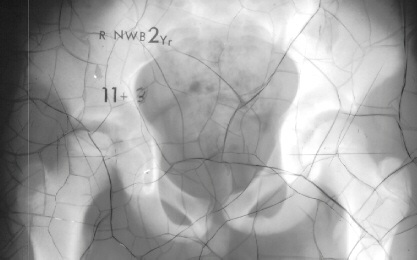

on the left side but the left hip pain was asymptomatic. X-rays 1 and 2

were taken at the age of 11 years and 3 months and xray 3 was taken at

12 years of age. At 16 years of age, 10 degrees limitation of internal

rotation as compared to the opposite side was still observed but the patient

was asymptomatic. X-ray 4 was taken at 17 years of age.